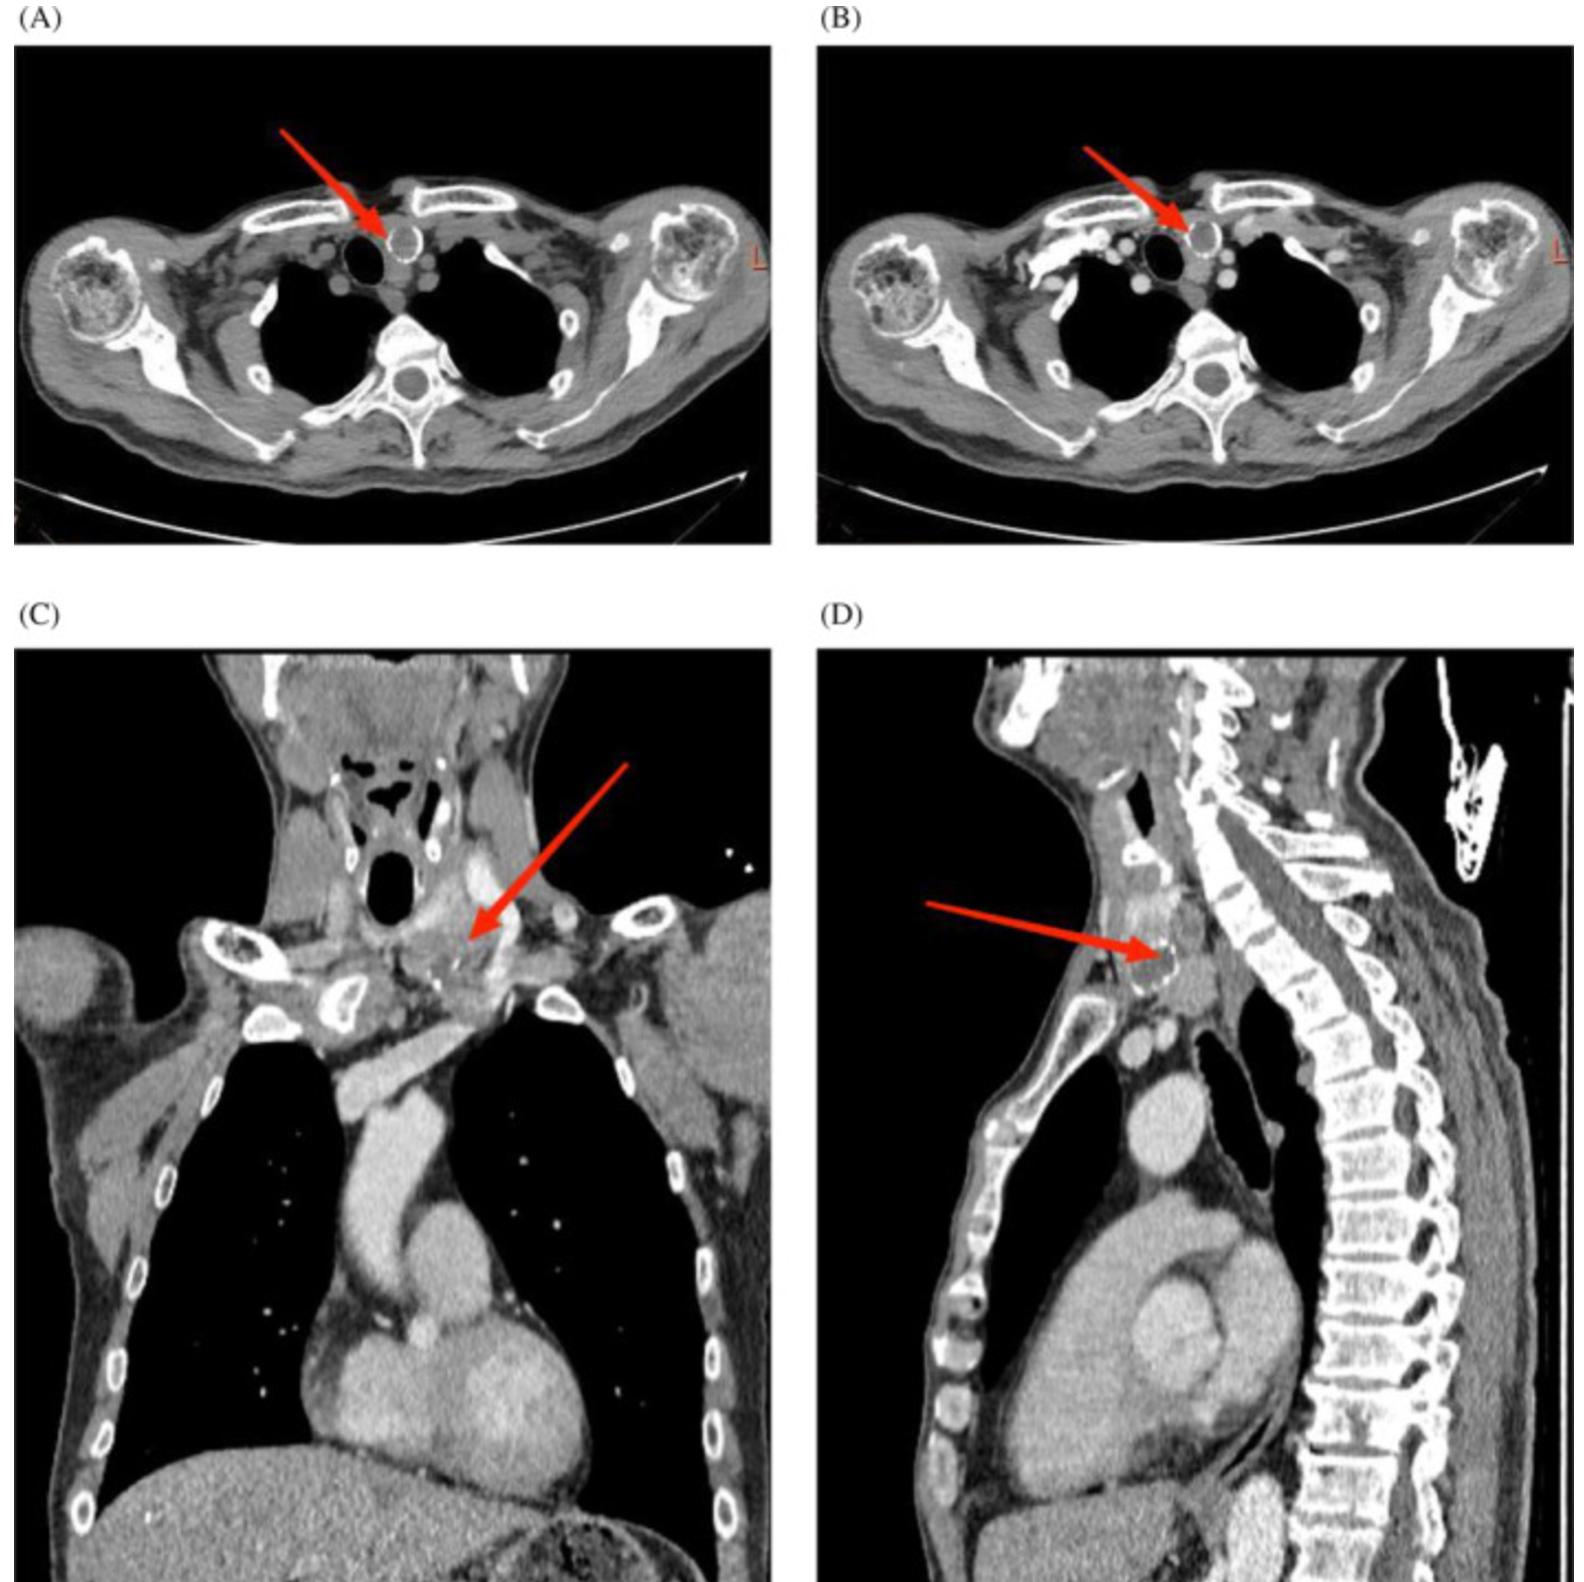

颈部超声(US)显示左侧甲状腺有3.5 cm×3.2 cm低回声肿块伴微小钙化点,左侧甲状腺下叶后方1.5 cm×1.5 cm低回声结节,边缘不明确,考虑到甲状旁腺起源的可能性;颈部计算机断层扫描(CT)和增强CT扫描显示左甲状腺叶增大,一3.4 厘米×2.8 cm不规则稍低密度影和圆形钙化灶向下突出至左侧气管旁间隙;左甲状腺下叶后部的1.3cm轻微圆形低密度阴影向后生长到食管前间隙,考虑为甲状旁腺肿块(图1)。

图1 颈部计算机断层扫描(CT)和对比增强计算机断层扫描:(A)CT显示左甲状腺叶增大,有不规则的轻微低强度阴影和圆形钙化灶,左甲状腺下叶后方有轻微圆形低强度阴影;(B) CECT显示左甲状腺叶低密度阴影增强扫描;(C) 甲状腺冠状位显示一个不规则形状的左侧颈部肿块向下突出到左侧气管旁间隙并压迫颈静脉;(D) 左甲状腺叶的矢状面显示乳头状肿块向后生长到食管前间隙